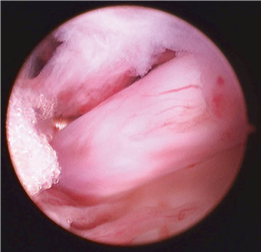

Clinical & Radiographic Imaging Archive

Clinical Image